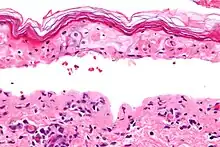

Micrograph of confluent epidermal necrosis. H&E stain.

Erythema multiforme major is a form of rash with skin loss or epidermal detachment.